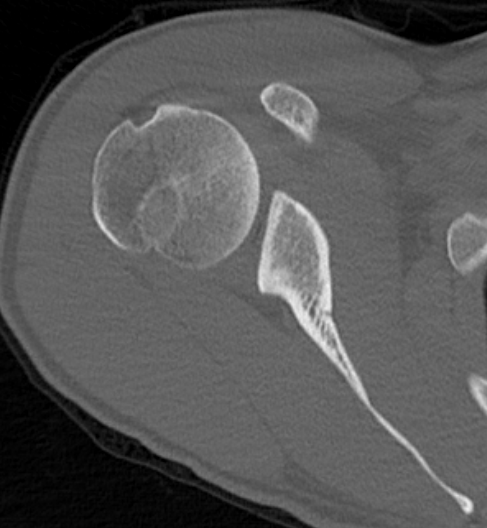

Reverse Hill Sachs / Posterior bony Bankart / Glenoid retroversion

CT

Hill Sachs lesion / posterior bony bankart / glenoid retroversion